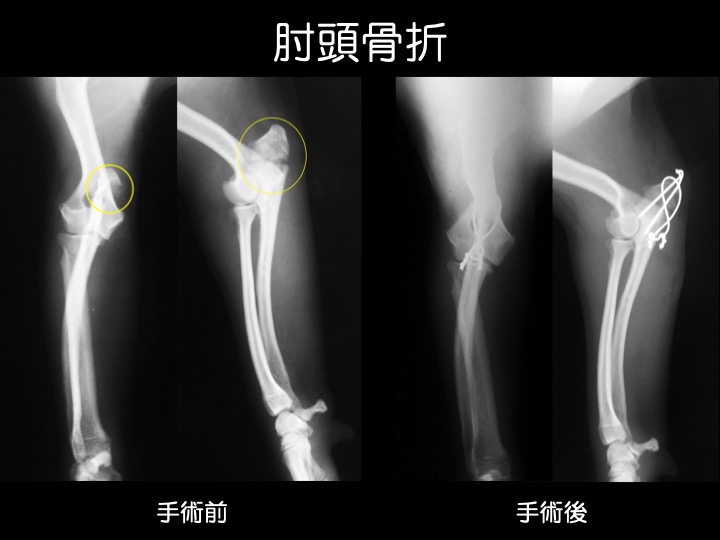

インプラント治療例

・骨折の治療は、ギプス、インプラントなどを用いて行われますが、これらはあくまでも、“骨折が治る=骨がくっつく” ための補助となるものです。

・治療には、適切な運動制限など、ご自宅での管理やケアが大変重要です。

・肘頭(ちゅうとう)は、「肘鉄(ひじてつ)」と呼ばれる肘の頂点の部分のことで、二の腕と前腕を繋ぐ蝶番の働きをし、肘の曲げ伸ばしを滑らかにする役割があります。

・ここが折れると、肘の機能や動きが損なわれ、腫れと激しい痛みを生じます。

・骨折による骨のズレが大きい場合や、ギプス固定ができない箇所の骨折などが適応になります。

・骨折の部位、動物の大きさや手術用途にあわせて選択できるよう、様々な種類のものが作られています。